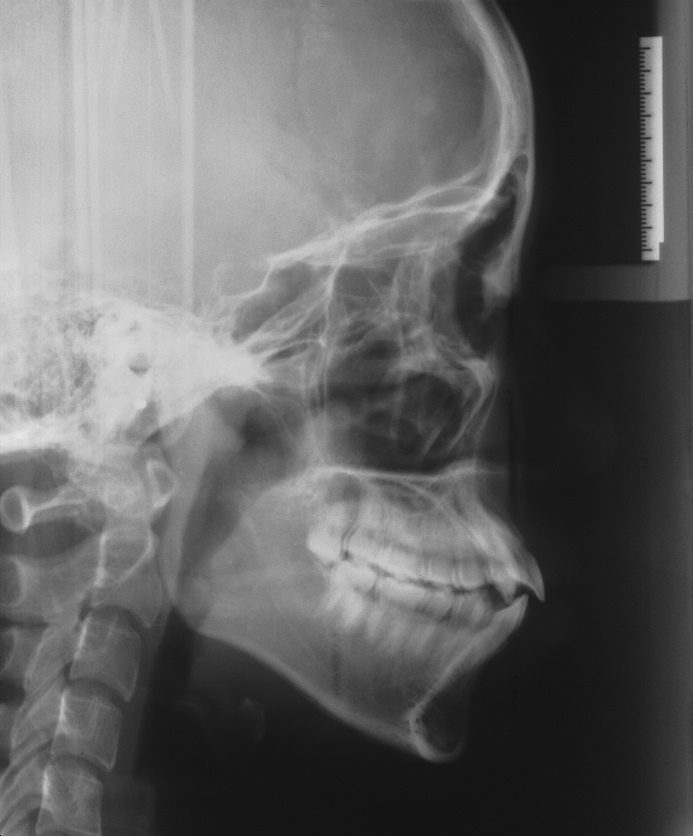

치료 전 사진입니다.